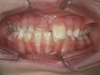

Mâchoire du bas en avant

Une mâchoire inférieure en avant, aussi connue sous le nom de prognathisme mandibulaire, se caractérise par une mâchoire inférieure qui dépasse la mâchoire supérieure. Elle peut être ou non d’origine héréditaire, et est toujours associée à une position basse de la langue. Dans certains cas, il ne s’agit pas d’une anomalie squelettique, mais d’un simple glissement de la mâchoire du bas vers l’avant provoquée par des incisives supérieures évoluées trop en arrière.

Pourquoi traiter ?

Un traitement précoce permet de rétablir des contacts incisifs efficaces nécessaires à une croissance osseuse optimale autour des incisives supérieures, une bonne position linguale, et le repositionnement de la mâchoire inférieure lorsqu’il s’agit d’un « glissement ». Dans les anomalies squelettiques vraies, le traitement précoce permet de diminuer le risque d’avoir recours à une chirurgie de mâchoire à l’âge adulte, et si on ne peut l’éviter, d’en améliorer le pronostic et le résultat.

Menton Avancé

Un menton avancé chez l'enfant peut traduire une anomalie squelettique vraie, ou un simple glissement vers l’avant de la mâchoire du bas lié à la position des dents. Dans tous les cas, un traitement précoce est nécessaire.